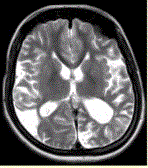

问题 女性,22岁。癫痫发作及智力异常。MRI显示见下图。 关于该病,最可能的原因是

选项 A.海绵状血管瘤 B.发育性静脉畸形 C.AVM D.毛细血管扩张症 E.动脉瘤 F.硬脑膜动静脉瘘 G.moyamoya

答案 CG